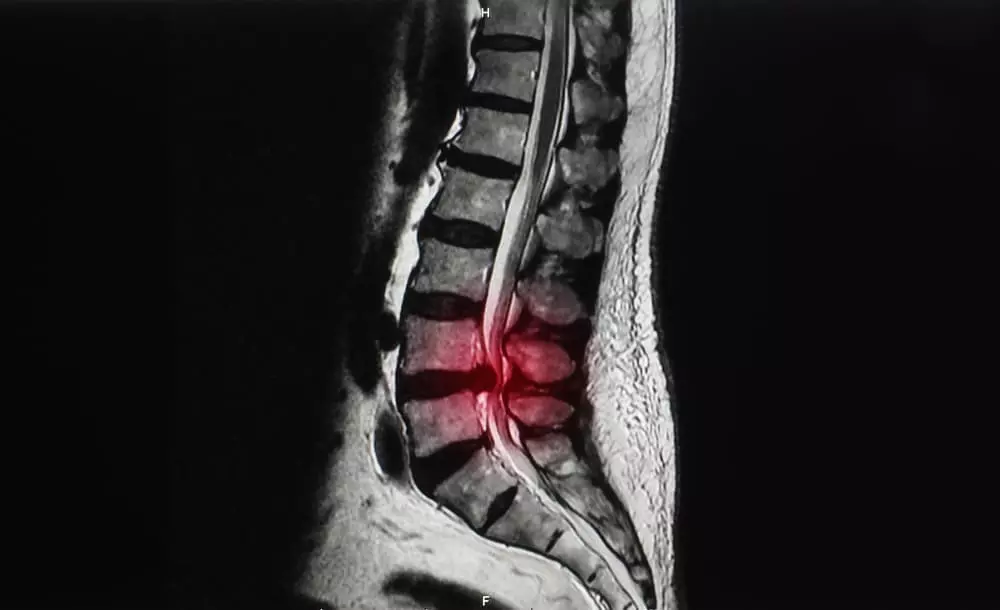

脊柱管狭窄症

背骨は、32から34個の椎骨が連なってできています。

その中には空洞があり、脊髄や血管が通る脊柱管と呼ばれる通路があります。

この脊柱管が何らかの理由で狭くなり、神経を圧迫することで、痛みやしびれといった症状が現れるのが脊柱管狭窄症です。